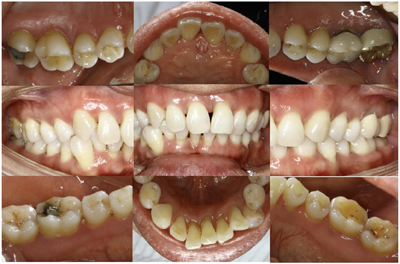

全口临床检查:口腔卫生状况一般,菌斑、软垢少量,下前牙舌侧可见新生牙石,龈下牙石(++)。牙龈色偏红,肿胀,形态圆钝,质软,尤以下前牙舌侧为重,出血指数3~4。全口牙齿探诊深度(PD)5~7 mm,个别位点8~9 mm。全口牙齿均可探及附着丧失,21、24、25、41、43松动I~Ⅱ。46合面金属色充填体,27烤瓷冠复体,近中悬突,可见食物嵌塞,叩痛(-)。咬合关系深覆合,下前牙多生牙,下前牙区拥挤,43位置颊倾,反合,见图1,图2,图3。

2016年6月1日后复查:口腔卫生状况一般,菌斑、软垢少量,龈下牙石(+-++)。牙龈色稍红,肿胀,形态稍圆钝,质软,出血指数3~。全口牙齿探诊深度(PD)4~6 mm,个别位点7~8 mm,较前略有改善。龈退缩2~3 mm,32~42Ⅰ~Ⅱo松动。48牙冠周围软垢较多,颊侧附着龈缺如(图6,图7,图8,图9,图10)。26远中龋坏,探诊敏感,冷热测激发痛,叩痛(-)。